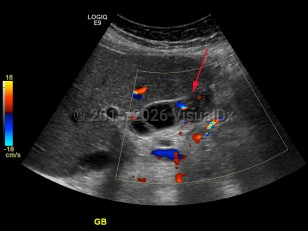

Gallbladder carcinoma